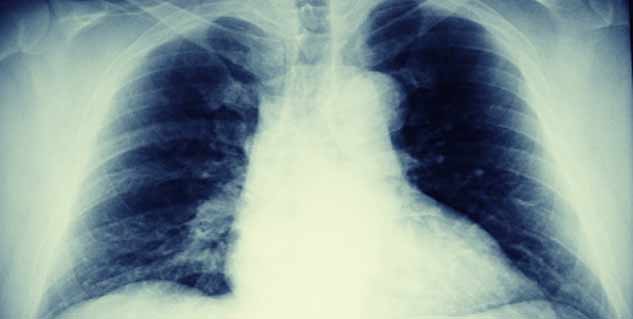

दिन प्रतिदिन बढ़ते प्रदूषण के स्तर का हमारे स्वास्थ्य पर बुरा असर देखने को मिल रहा है। वायु प्रदूषण न सिर्फ वातावरण को प्रदूषित करता है बल्कि यह हमारे शरीर में होने वाली कई जानलेवा बीमारियों की जड़ है। इसकी वजह से फेफड़ों से संबंधित रोग होते हैं। अस्थमा, सांस फूलना, एलर्जी आदि रोगों का कारण स्मॉग और वायु प्रदूषण है। प्रदूषण से हमारे फेफडों को होने वाले नुकसान से बचाने के लिए कुछ फूड्स बताए गए हैं, जिनका सेवन कर अस्थमा को कंट्रोल किया जा सकता है।

फेफड़ों के स्वास्थ्य के लिए 7 बेहतरीन फूड्स